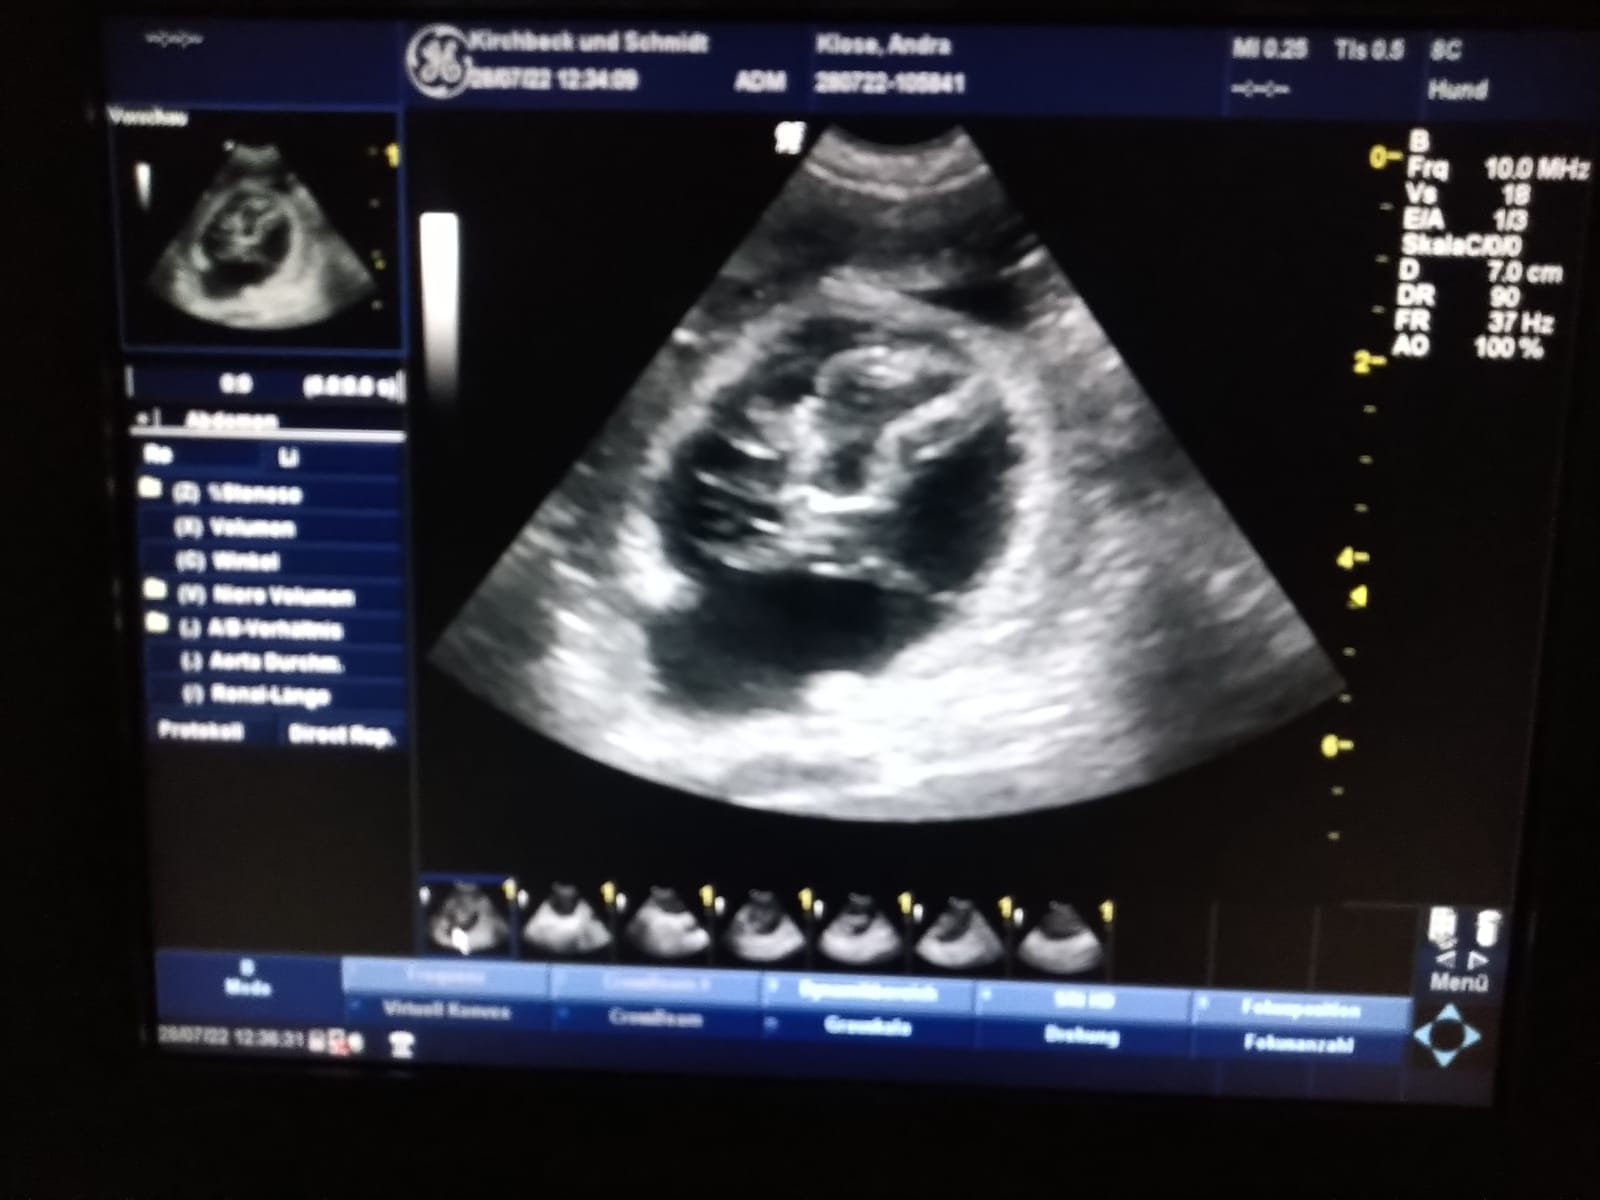

Die Ultraschalluntersuchung war negativ...

leider keine guten Nachrichten für uns und unsere Welpen-Interessenten

Wir und auch die Besitzer von Atwood, Silke und Andreas, sind ganz traurig. Beide, Ida und Atwood, waren fit und gesund und der Deckzeitpunkt lt. Tierärztin genau richtig. Aber nach der Enttäuschung blicken wir nach vorn, wie so viele andere Hündinnenbesitzer zur Zeit ebenso. Im Herbst gehen wir es wieder an und freuen uns, wenn der ein oder andere Interessent bei uns bleibt.